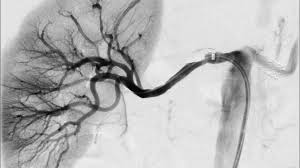

Hypertension, or high blood pressure, is another leading cause of kidney failure. When blood pressure remains consistently high, it can damage the blood vessels in the kidneys, reducing their ability to filter waste and maintain fluid balance. This condition, called hypertensive nephropathy, can lead to kidney failure over time.

Dr. David Miller, a cardiologist, notes, "Chronic high blood pressure can cause the arteries in the kidneys to narrow, weaken, or harden, making it difficult for the kidneys to effectively filter waste. This ultimately leads to kidney damage."